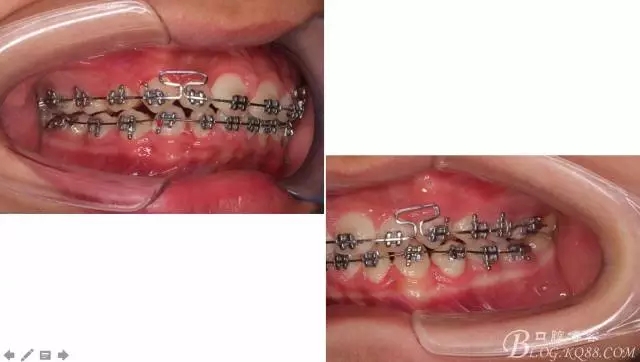

佩戴三個月的FR2, 效果奇佳!前牙基本達到淺覆蓋,淺覆合!接下來進入二期直絲弓固定正畸,排齊階段!

接下來盡管配合些雙側(cè)后牙對角牽引,咬合關系依,不盡人意。

下頜配合多曲方絲,三角牽引,調(diào)整咬合。

中線不齊,咋辦?繼續(xù)哄哄患者配合,2牽+斜牽。

努力沒有白費,中線基本對齊!